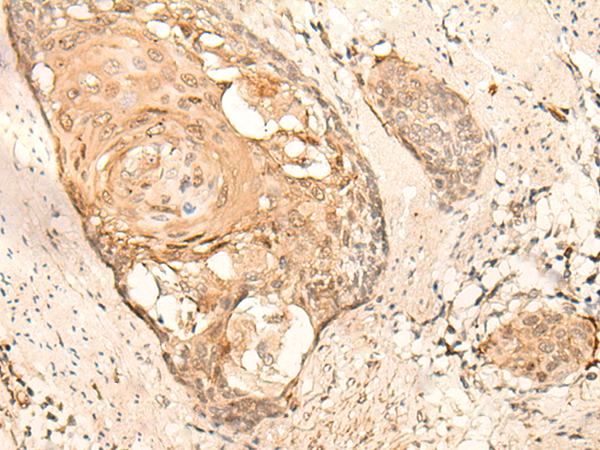

Applications: |

ELISA, IHC |

IHC positive control: |

Human esophagus cancer and Human breast cancer |

IHC Recommend dilution: |

25-100 |